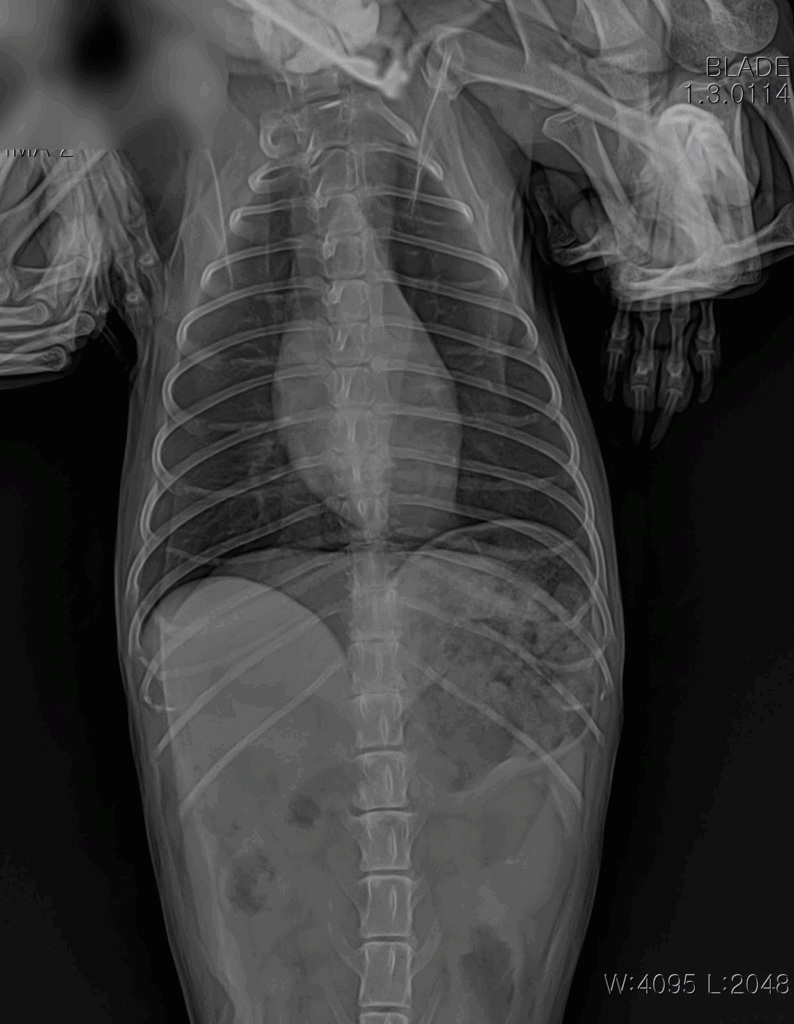

📌 흉부 X-ray

X-ray 촬영은 심장의 크기와 모양, 그리고 폐에 물이 차 있는지 여부를 확인하는 데 사용됩니다. 이를 통해 심장비대나 폐수종 같은 합병증 여부를 빠르게 파악할 수 있습니다.

내원 즉시, 적극적인 산소처치와 안정화가 먼저 이루어졌습니다. 호흡곤란 환자는 응급 상황으로 진행될 수 있기 때문에, 빠른 산소 공급과 안정을 통해 위험을 줄이는 것이 최우선입니다. 이후 상태가 안정되자 심장 초음파와 흉부 방사선을 통한 정밀 진단이 진행되었습니다.

내원 당시 흉부 방사선 사진: 심장 비대 및 폐수종 확인